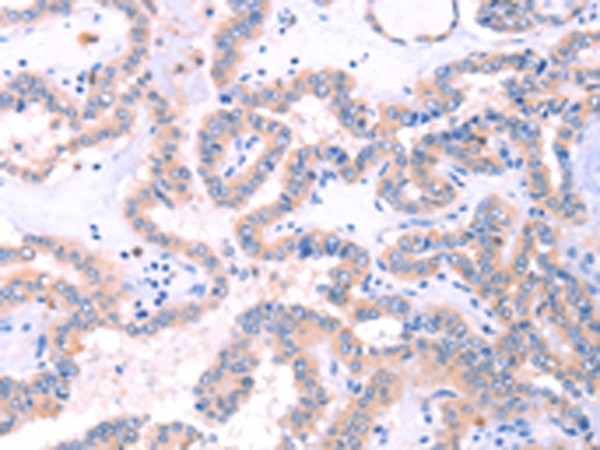

分类: 科研抗体货号: P07712别名: NR1I1; PPP1R163应用: IHC反应种属: Human, Mouse, Rat